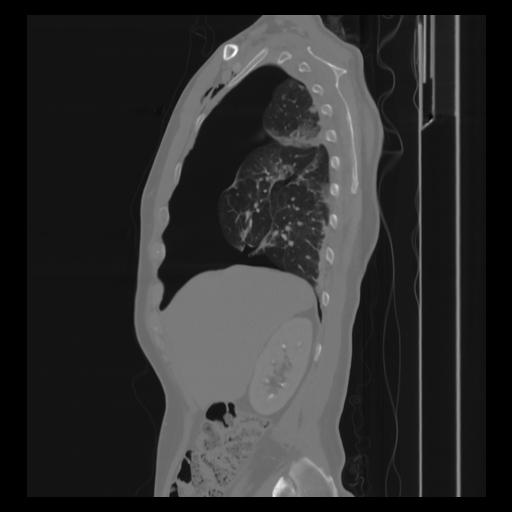

30 CUERPO,CE,Sagittal,3.000,CUERPO,Sagittal,